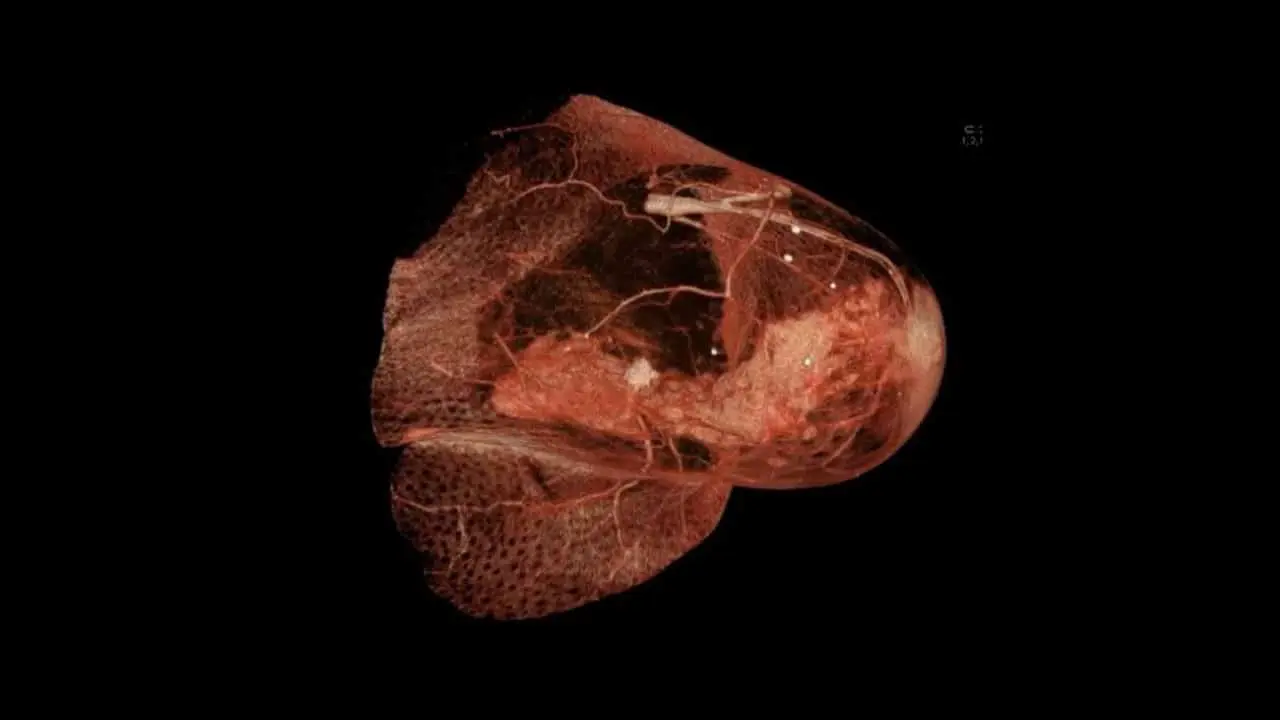

Отсутствие уязвимых мишеней значительно осложняет лечение. Поэтому современные ученые фокусируются не только на злокачественных клетках, но и на всей их экосистеме: соединительной ткани, иммунных клетках, сосудах. В совокупности это формирует уникальную среду – опухолевое микроокружение, способное как подавлять, так и активизировать раковый рост.

Анализ показал удивительный факт: основной источник стимулирующего опухоль белка IGF2 – не злокачественные клетки, а фибробласты. Эти клетки соединительной ткани, часть микроокружения, в нормальных условиях поддерживают тканевую структуру, но при болезни способствуют прогрессированию рака. Однако природа предусмотрела естественный контрмеханизм. Регуляторный белок IGFBP6 действует как ловушка для IGF2, сдерживая его разрушительную активность. Важно, что IGFBP6 вырабатывается как окружением опухоли, так и частично ею самой в попытке ограничить неуправляемый рост.